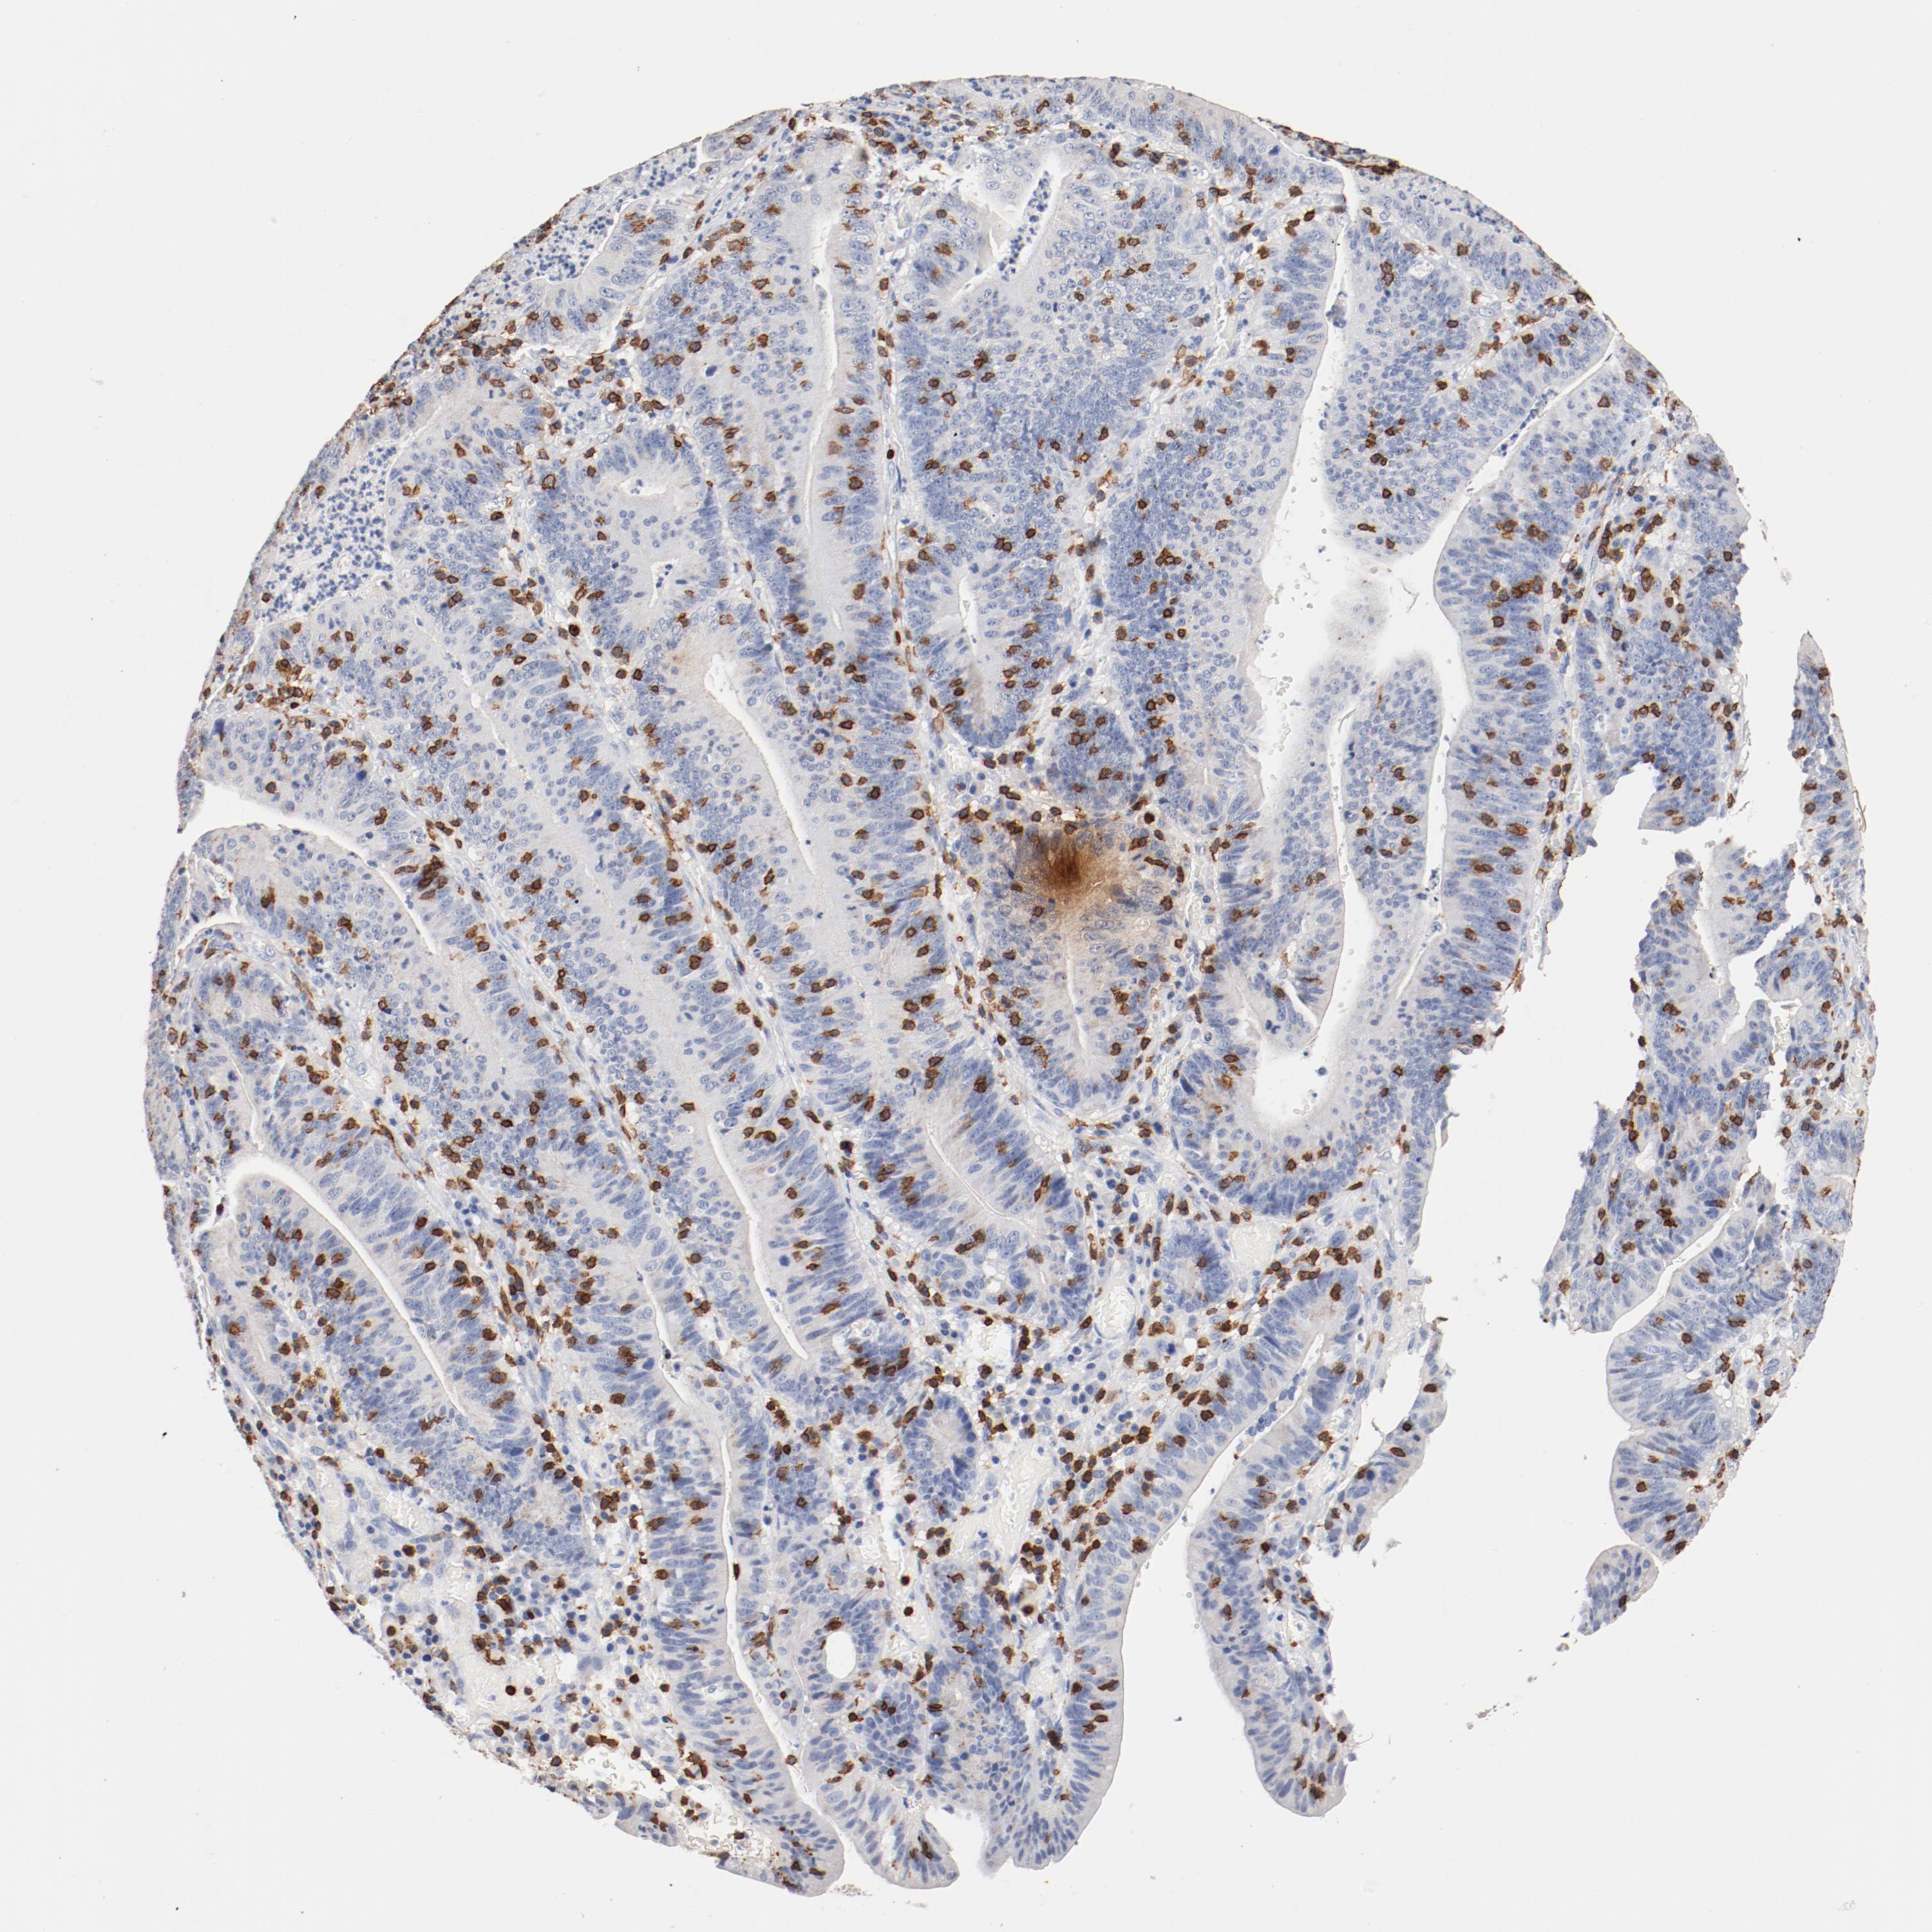

STOMACH CANCER - Protein expressioni

A mouse-over function shows sample information and annotation data. Click on an image to view it in a full screen mode. Samples can be filtered based on level of antibody staining by selecting one or several of the following categories: high, medium, low and not detected. The assay and annotation is described here.

Note that samples used for immunohistochemistry by the Human Protein Atlas do not correspond to samples in the TCGA dataset.

Antibody stainingi

Antibody staining in the annotated cell types in the current human tissue is reported as not detected, low, medium, or high, based on conventional immunohistochemistry profiling in selected tissues. This score is based on the combination of the staining intensity and fraction of stained cells.

Each image is clickable and will lead to virtual microscopy that enables deeper exploration of all samples and also displays staining intensity scores, fraction scores and subcellular localization as well as patient and tissue information for each sample.

Antibody HPA008750

Antibody CAB004651

Staining

High

Medium

Low

Not detected

Intensity

Strong

Moderate

Weak

Negative

Quantity

>75%

75%-25%

<25%

None

Location

Nuclear

Cytoplasmic/membranous

Cytoplasmic/membranous,nuclear

Adenocarcinoma, NOS

Adenocarcinoma, High grade